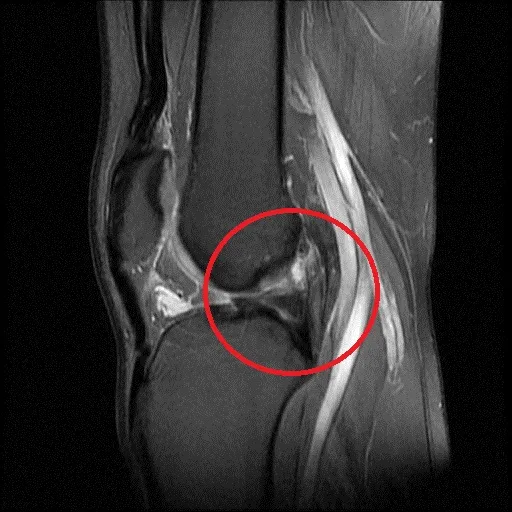

患者因十字韌帶斷裂(紅圈處)險些斷送籃球夢。院方提供

蘇皇儒解釋,「前十字韌帶」負責膝關節前後和旋轉的穩定度,本身是十分粗壯的韌帶,平常走路時不容易斷裂,但若從事籃球或足球等運動,這類運動需要快跑、急停、煞車及轉身等動作,會有側向外力對膝蓋施加撞擊,因此對十字韌帶展生扭力因而造成斷裂。